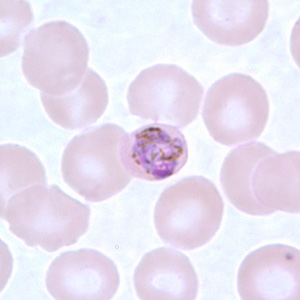

Babesia